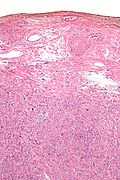

Microscopic

Features:

- Spindle cells arranged in fascicles.

- Fascicular appearance: adjacent groups of cells have their long axis perpendicular to one another; looks somewhat like a braided hair that was cut.

- Whorled arrangement of cells.

- +/-Medium-sized artery seen at the periphery of the lesion.

- Often arise from a muscular artery.

The section shows unremarkable hair-bearing skin with a well-circumscribed subcutaneous lesion with a fascicular architecture. The lesion has no nuclear atypia and no mitotic activity is identified. At the periphery of the lesion is a medium-sized muscular artery from which the lesion appears to arise.